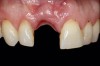

(13.) Postoperative image of site No. 8 taken 4 months after extraction and grafting.

Figure 13

When the patient returned 4 months after the initial procedure for reevaluation, she underwent supportive periodontal therapy and was provided with detailed oral hygiene instructions (Figure 13). An intraoral scan and a postoperative CBCT scan were taken to evaluate both the horizontal and vertical hard- and soft-tissue gain. Next, implant planning software was used to merge the STL and DICOM data, which facilitated the creation of a digital wax-up (Figure 14).